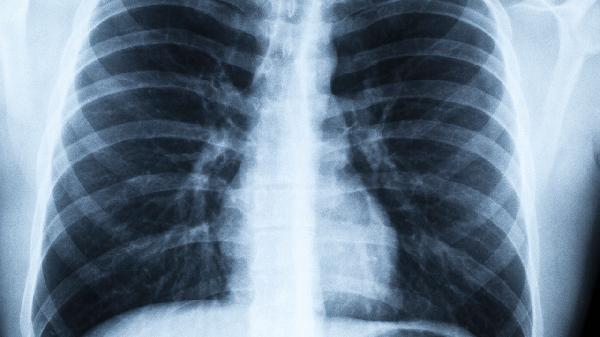

肺不好真让人发愁?日常饮食调整能帮大忙?适当补充营养或可缓解肺负担

秋风起,肺先知。每到这个季节,总有人开始频繁清嗓子、半夜咳醒,甚至爬个楼梯都气喘吁吁。其实我们的肺就像精密的空气净化器,需要定期“保养”。与其等出了问题再着急,不如从每天的三餐开始温柔呵护它。